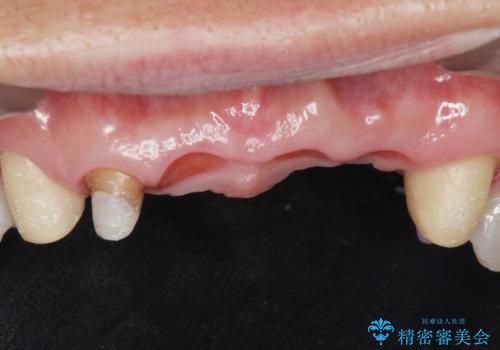

左上の側切歯(左上2)を抜去し、右上の側切歯(右上2)の再根管治療後、セラミックのブリッジによる補綴を行いました。